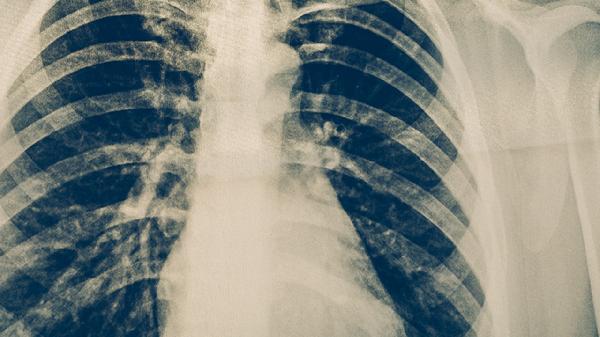

肺结核复发早期ct能看出来吗

肺结核复发CT检查一般是可以看出来的。但是由于病情的严重程度不同,所以具体的情况也是因人而异。1.可以看出来:肺结核是由结核杆菌感染引起的慢性传染性疾病,具有一定的潜伏期,在发病期间患者可能会出现咳嗽、咳痰、身体乏力等症状。如果在患病后没有及时进行治疗,并且个人免疫力比较低下,则会导致疾病进一步加重,从

判断肺结核是否复发的方法较多,通常包括临床症状、影像学检查、实验室检查等。如果怀疑自身存在肺结核复发的情况,则建议及时前往医院就诊。一、临床症状:当患者出现咳嗽、咳痰时间较长或伴有咯血等症状时,可能提示病情复发。若患者出现午后低热、夜间盗汗以及身体消瘦等情况,也可能为肺结核复发的表现。二、影像学检查